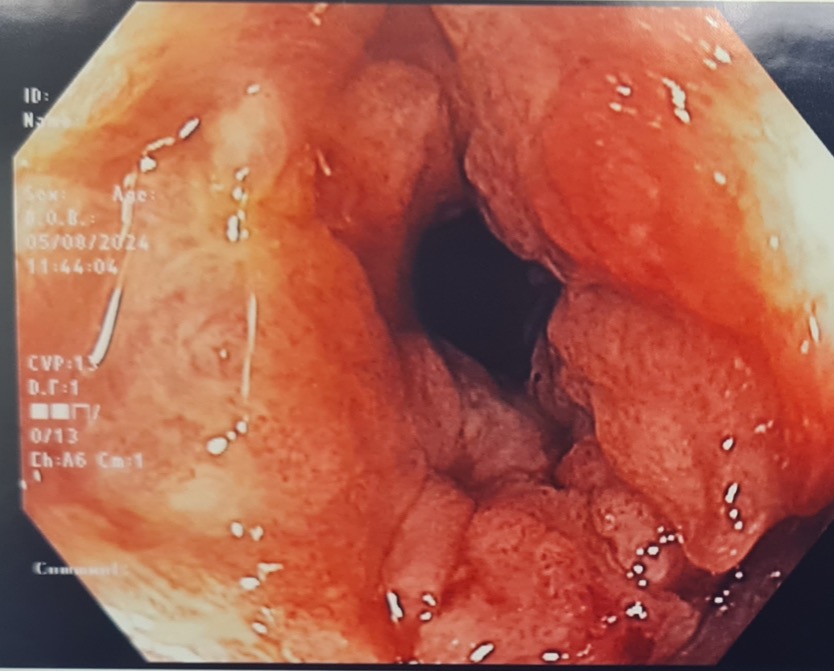

Pre-treatment image of anal mass seen during colonoscopy